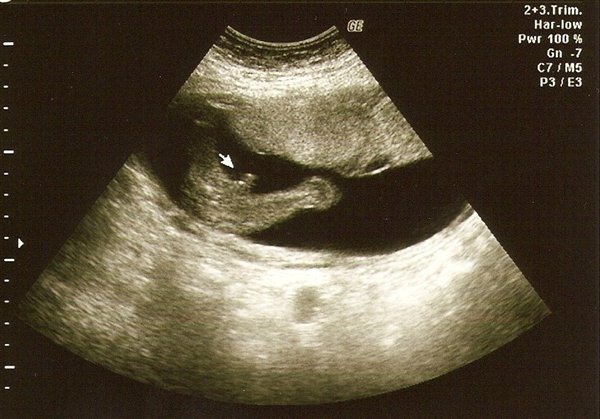

Se der hvor pilen pejer!

Vedhæftede fotos (klik for at se i fuld størrelse)

Det er et drengebillede?

Også i den grad... Som hun pænt sagde der var vist ingen tvivl...